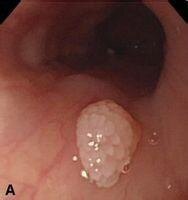

食管乳头状瘤

一、什么是食管乳头状瘤?1、食管乳头状瘤是一种出现在食管的良性上皮病变,呈息肉样隆起,其组织学特征是由数量增加的鳞状细胞排列而成的指状突出组织。2、可以发生于食管的任何位置,但大约70%的乳头状瘤发生于远端1/3食管。3、该疾病罕见,在接受上消化道内镜检查的患者中其发病率为0.01%-0.45%。二、食管乳头状瘤的病因有哪些?迄今为止,食管乳头状瘤的病因和发病机制仍不清楚。目前比较倾向性的一些病因包括:1、黏膜损伤及局部炎症刺激(1)已证实胃食管反流病、食管炎、食管裂孔疝或黏膜刺激(例如,鼻胃管留罝、探条辅助性食管机械扩张等机械操作)与食管乳头状瘤的发生有关。(2)此外,动物研究显示,苯并芘和亚硝胺类所致的腐蚀性黏膜刺激可以诱发乳头状瘤。2、人乳头状瘤病毒(humanpapillomavirus,HPV)感染一些临床研究显示HPV感染可能与食管乳头状瘤形成有关,但是不同研究机构的数据存在较大的差异。意大利的研究显示HPV存在于21%-46%的食管乳头状瘤患者中,而美国的研究则发现HPV存在于不到5%的病例中。(2)另外有研究发现,部分食管乳头状瘤病例与HPV血清型6型和11型(这两型主要在人类口咽部和生殖道中发现)相关,提示这部分病例可能为性传播所致。(3)HPV在食管癌发病机制中的作用仍不明确。部分研究发现,一些食管鳞状细胞癌中可以检测到HPV。然而,目前仍缺乏食管HPV感染导致食管癌变的直接证据。三、食管乳头状瘤患者有哪些临床表现1、年龄食管乳头状瘤最常发生于50以上患者,但是近年来随着内镜检查的普及,越来越多的年轻人被检出食管乳头状瘤。2、性别部分研究报道显示男性发病率高于女性,部分研究则提示发病率在不同性别人群分布相当。尚缺乏较大规模人群统计数据结果。3、症状(1)大多数食管乳头状瘤病变并不直接引起症状,但较大的病变可导致吞咽困难。(②一般情况下,患者的症状(上腹不适、疼痛、腹胀、胸骨后烧灼感、胸闷)往往与同时伴发的其它消化系统疾病有关,例如:食管裂孔疝、反流性食管炎、消化性溃疡等。四、食管乳头状瘤在胃镜下有哪些特点?1、食管全程(上、中、下段)均可发生食管乳头状瘤,但多见于中下段食管。2、呈乳头样、分叶状、球形或半球形小突起,表面颗粒样。3、可表现为无蒂、有蒂或亚蒂。4、色泽近似食管黏膜颜色,呈灰白色或浅粉红色,质地柔软,弹性好。5、肿块多较小,直径为0.2cm-1.0cm,但也有报道最大直径达3.0cm的病变。6、大多数乳头状瘤是孤立性的,但是也有报道存在超过10个病变的患者。了、卢戈氏碘液染色后显示与正常黏膜一致的良好着色。五、如何确诊食管乳头状瘤?1、确诊依据典型的内镜下形态学表现+病理学证据。2、食管乳头状瘤的病理特点(1)表层为增生的复层鳞状上皮,有品著的角化过程,中间为血管结缔组织。(2)鳞状上皮具有正常的细胞极性和分化,无分化不良。六、食管乳头状瘤该怎么治疗?1、目前无特效的药物治疗。2、EP的治疗主要是内镜下治疗:(1)活检钳除术:适用于直径小于0.5cm的病变。(2)微波、射频消融术:适用于直径小于0.5cm的病变。(3)氩离子凝固术:适用于直径小于0.5cm的病变。(4)高频电凝电切术:适用于直径0.5cm-1.0cm的病变。(5)内镜黏膜切除术(EMR):适用于直径大于1.0cm的病变,尤其是无蒂、宽基底病变。七、食管乳头状瘤会癌变吗?治疗后会不会复发?1、目前认为食管乳头状瘤是一种良性病变,临床随访尚末发现癌变病例。2、经内镜下治疗后极少复发;临床上发现多发性食管乳头状瘤治疗后部分会复发,但也可能是治疗不彻底导致的复发。总体来说,食管乳头状瘤经内镜下治疗后一般预后良好。